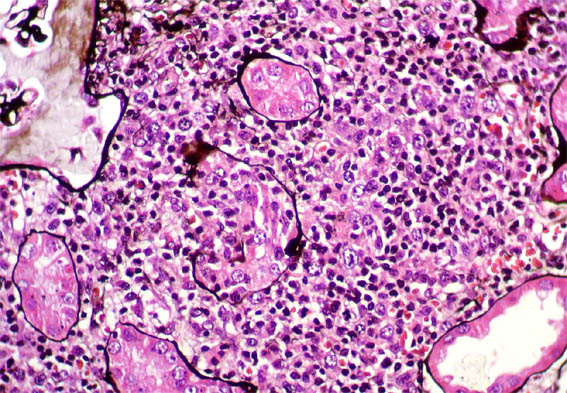

H&E, X100.

Figure 3. H&E, X200.